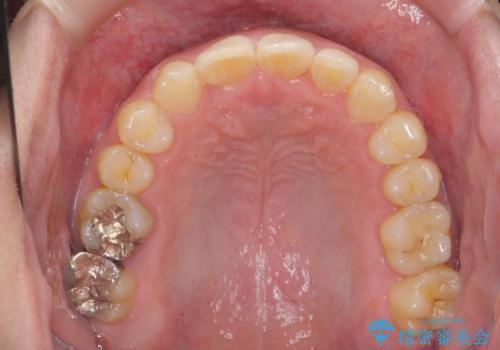

前歯のすき間 歯のがたつき

- 前歯のすき間とがたつきを主訴に来院。

右上の前歯は過去にがたつきがあったとのことで抜いてしまっていました。

歯の数を合わせるために、下の歯を1本抜いて矯正しています。

下の前歯を抜歯したことでブラックトライアングルができましたが、仕上げにIPRを加えることで目立たなくすることができました。